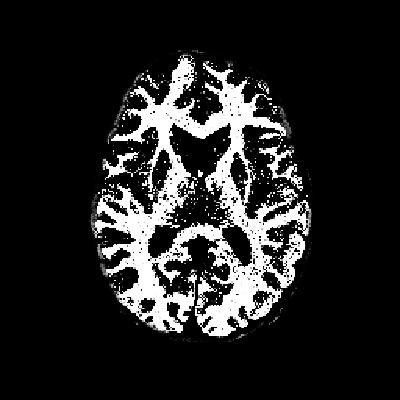

- 掩膜图像:如图2所示,掩膜图像指示了图像中感兴趣区域的位置,从而帮助我们仅对目标区域进行分割。

从代码中可以看出,我们首先加载了一个.mat格式的数据文件,其中包含了待处理的图像img和掩膜图像mask。掩膜图像的作用是指示图像中感兴趣区域的位置,从而帮助我们仅对目标区域进行分割,而忽略背景噪声。